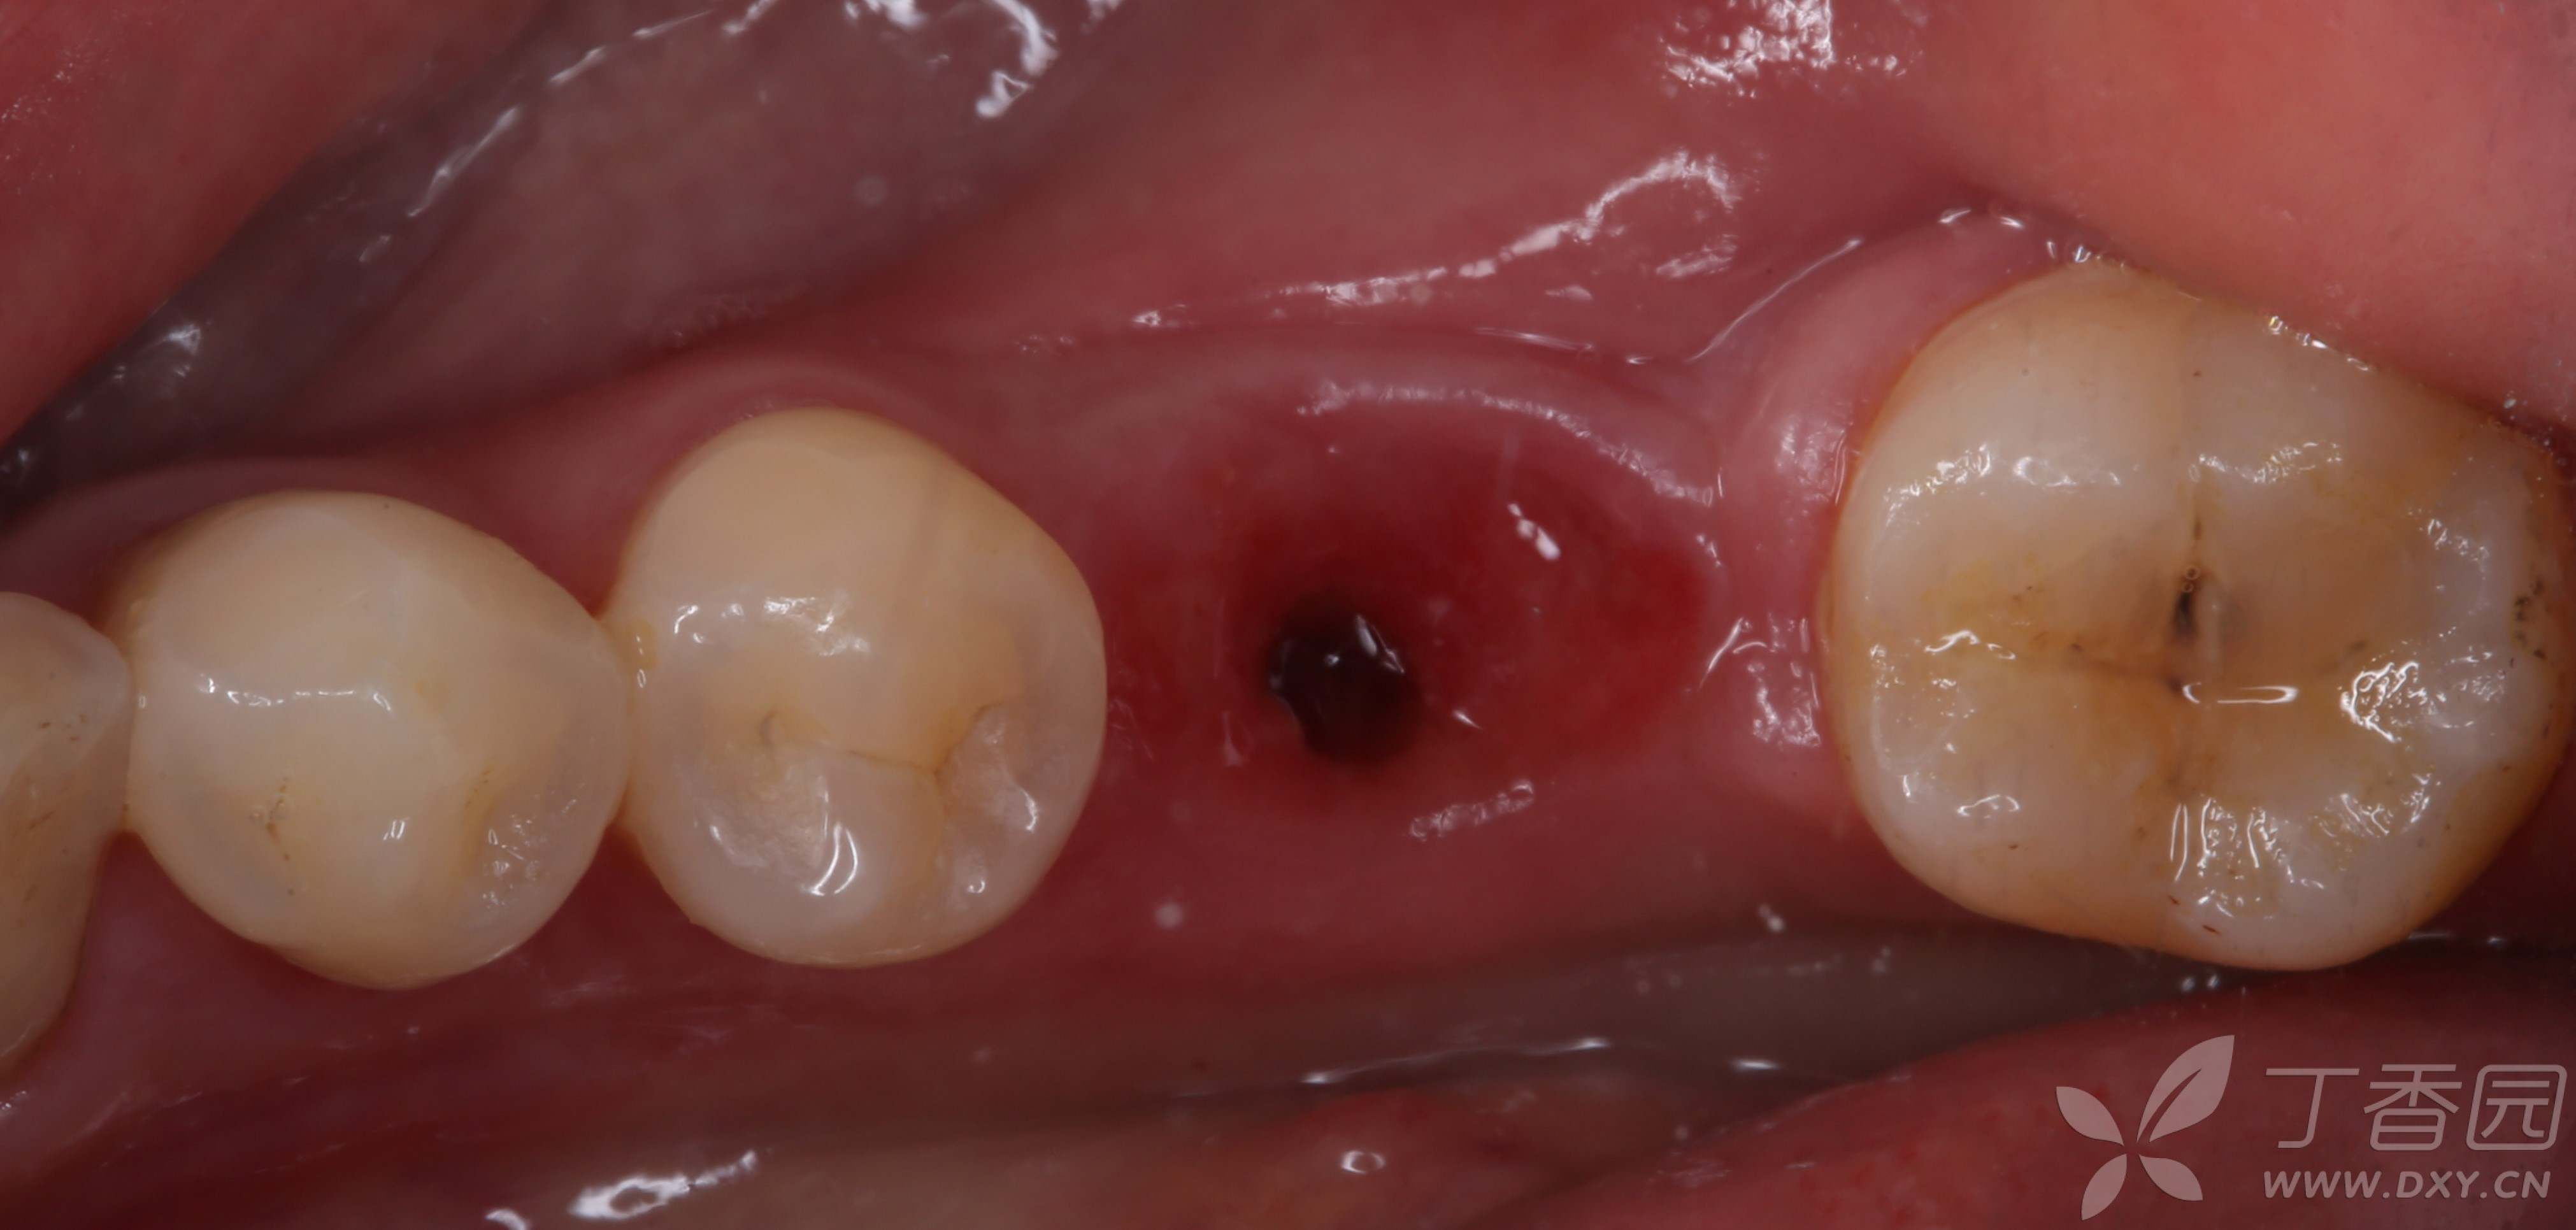

种植体取出后,袖口可见大量肉芽组织。

取出种植体,刮净肉芽组织,碘酊灼烧,生理盐水,洗必泰大量冲洗,缝合,嘱3个月后复查。